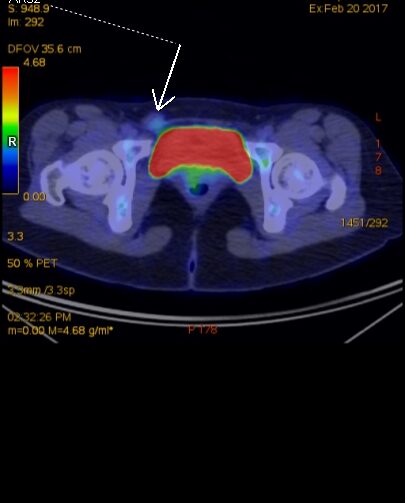

Figura 1: axial PET-CT la diagnostic iniţial

Endometrioza este o patologie benignă dar cu rată de recurentă mare; cazul prezentat este al unei paciente cu o leziune expansivă de perete abdominal inferior în vecinătatea regiunii inghinale drepte pentru care a efectuat examinare PET CT pentru diagnostic și stadializare datorită suspiciunii de adenopatie de la un melanom malign – iar leziunea nu a avut captare foarte mare. După excizie și examen histopatologic diagnosticul a fost de focar de endometrioza iar examinarea postoperatorie prin rezonanță magnetică nu a evidențiat un rest sau o recidivă locală. Câțiva ani mai târziu se remarcă creșterea volumului local și examinarea prin rezonanță magnetică evidențiază un aspect tipic de endometrioză.